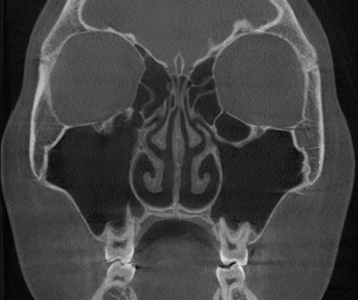

재수술 후